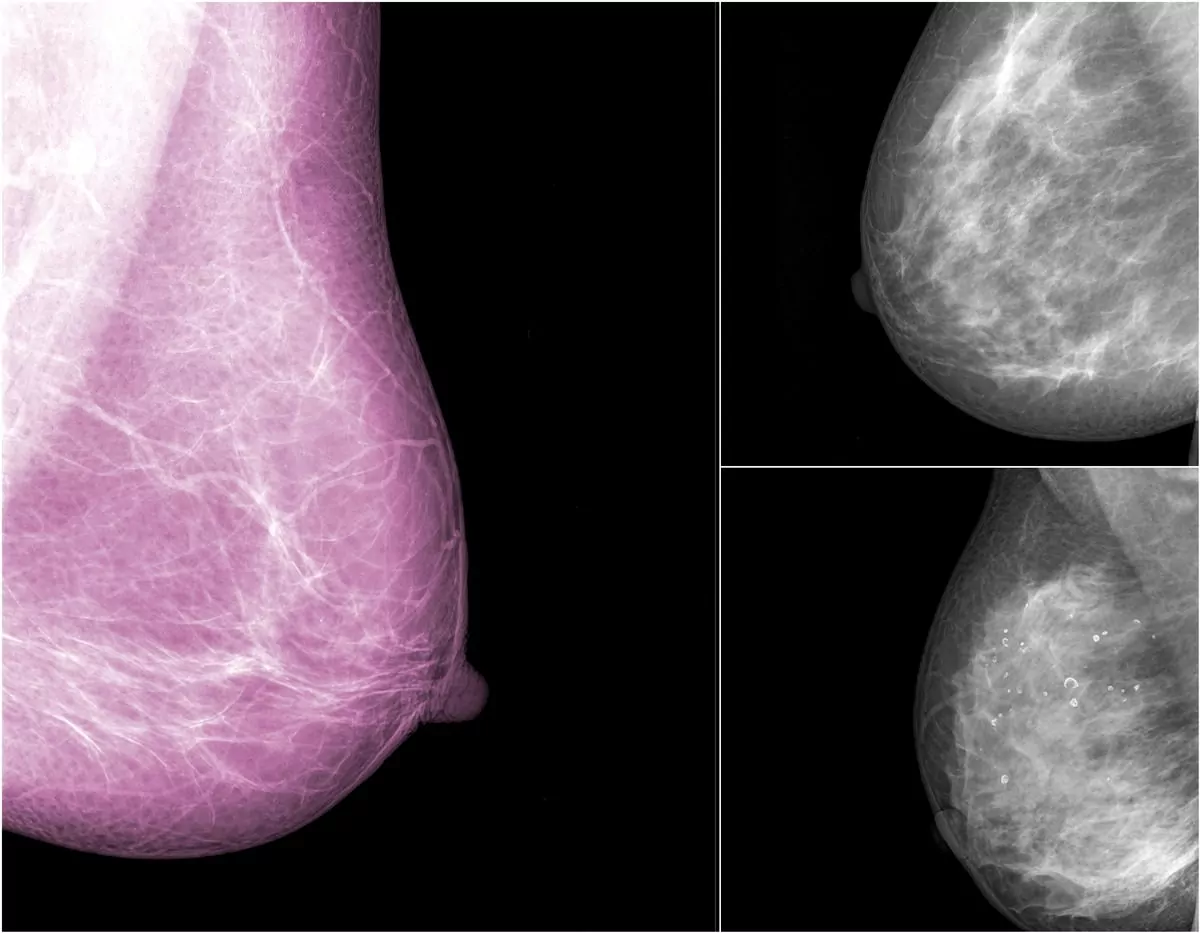

- Une mammographie est une radiographie des seins qui permet de détecter un cancer du sein

Il est recommandé tous les deux ans et consiste à réaliser une mammographie et à pratiquer un examen clinique des seins.

Dans le cadre du programme de dépistage organisé, une seconde lecture systématique des mammographies jugées normales est assurée par un second radiologue expert.